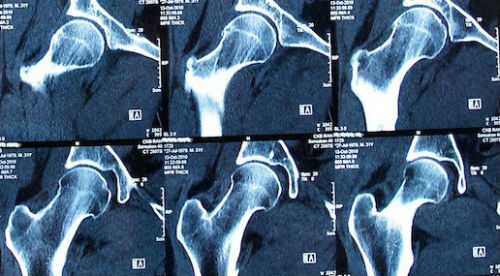

Методом выбора является рентгенография тазобедренного сустава в прямой и боковой проекциях. Это позволяет исключить переломы. Однако, в некоторых случаях, даже если рентгенологическая картина в норме, требуется проведение дополнительных исследований, например, КТ или МРТ тазобедренного сустава, с целью исключения скрытых переломов или повреждения мягких тканей.

В сложных случаях КТ может быть полезна для получения дополнительной информации, которая необходима при планировании операции. Также стоит учитывать, что интерпретация рентгеновского снимка будет осложнена у пожилых людей наличием других состояний, например, дегенеративных процессов.

Рентгенограмма как метод исследования рассчитана на визуализацию костных структур. При диагностике хорошо просматриваются:

- Сустав. Выявляют вывихи, подвывихи, расширение суставной щели, сужение или сращение с формированием анкилозов.

- Головка бедренной кости. Просматривается вертел, шейка бедра, выявляются трещины, переломы, аномалии развития и строения, остеомиелитные и остеопорозные изменения.

- Переломы и трещины. На рентгене можно рассмотреть локализацию травмы, наличие смещения и количество отломков и осколков, степень смещения костных структур.

- Вывихи. Визуализируется выход большого вертела бедренной кости из суставной поверхности вертлужной впадины.

Наиболее точным и информативным инструментальным методом диагностики состояния таза является МРТ. Действие основано на прохождении электромагнитного излучения и радиочастотных волн через организм человека. В результате взаимодействия с протонами, содержащимися в тканях исследуемой области, образуется сигнал, который улавливают датчики аппарата МРТ. Полученная информация преобразуется в послойные изображения, которые дают возможность построения объемной 3D модели суставных частей таза.

Исследование дает информацию о малейших изменениях, происходящих в суставных тканях, позволяет установить точный диагноз уже имеющихся заболеваний. На снимках можно детально рассмотреть и оценить состояние хрящевого покрытия суставных поверхностей, капсулы сустава, связок и сухожилий, мышечного аппарата. Метод выявляет воспалительные, дегенеративные, онкологические процессы, позволяет уточнить диагноз в более чем 95% случаев.

МРТ бедра показывает отек костного мозга, участки некроза под суставным хрящом с образованием серповидной полоски. На третьей-четвертой стадии отмечаются признаки импрессионного перелома, сужение суставной щели, костные разрастания, склероз и кисты в головке бедра. Изменения сустава необратимы — формируется грибовидная форма головки, деформация шейки, сглаживание суставных поверхностей.